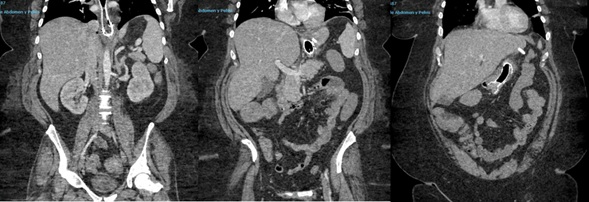

Caso clínico: Mujer de 53 años con antecedentes de sleeve gástrico en 2013, intervenida de re-sleeve gástrico en centro privado hace dos meses. Consulta por epigastralgia, vómitos y oliguria. Se realiza TAC (tomografía axilal computarizada) de abdomen que evidencia fuga de contraste cercana a cadeneta quirúrgica sugestiva de dehiscencia de sutura. Ingresa para endoscopia digestiva alta, identificando dos soluciones de continuidad de unos 4 mm, colocando prótesis totalmente recubierta de 14 cm ante la no disponibilidad de megastent. La paciente presenta mala tolerancia a la prótesis, junto con persistencia de vómitos y epigastralgia, se repite TAC evidenciando migración proximal de la prótesis. Se plantea retirada de la prótesis al 7.º día tras su colocación y posicionamiento de SNG de alimentación hasta disponibilidad de megastent dos semanas después. Se comprueba buen paso a través de la misma mediante tránsito contrastado con Gastrografín. Se procede al alta hospitalaria con buena tolerancia oral al 5.º día tras colocación de la prótesis.